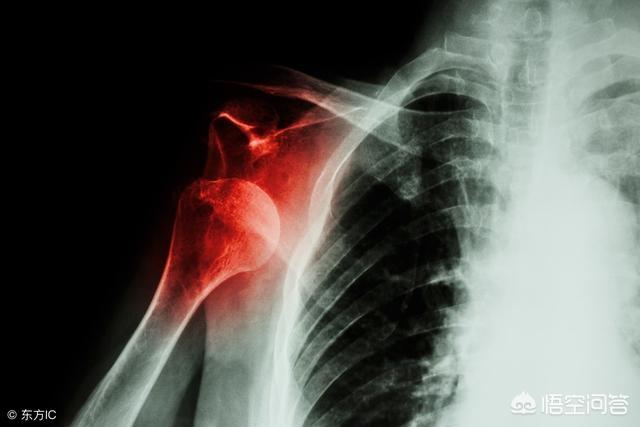

肩関節には、肩峰と上腕骨の大結節という非常に重要な構造があります。肩峰と上腕骨大結節間のインピンジメントの可能性これは肩の痛みの非常に一般的な原因である。肩のインピンジメント症候群。通常、X線検査で判断できる。レントゲンフィルムを見ると、過形成のようなインピンジメントの跡が見えます。下の写真を見るとよくわかると思いますが、赤い印が過形成、黄色い印が鉤状の肩峰です。赤い印は骨の増殖で、黄色い印は鉤状の肩峰です。インピンジメントが緩和されずに悪化すると、肩峰と大結節の間にある重要な構造物である腱板を骨折する危険性が高いため、肩関節インピンジメント症候群の患者には立位での肩のダンピングリハビリは勧められません。

肩のインピンジメント症候群の管理は、早期に肩の筋肉の運動、症状を制御するための局所的な薬を強化するために取ることができる、あなたが痛みを和らげるために患者を助けるために肩関節の治療のカプセル内注射を実施するために与えることを試みることができる場合。保存的治療を行っても症状が改善しないため、肩峰の鉤状部分を切除してインピンジメントを完全に解消するために、関節鏡視下手術が必要になることもあります。。

これを見るのが心配な人は、このようなことがあることを理解しておく必要がある。構造上の問題この問題は、肩関節周囲の軟部組織へのインピンジメントが原因である可能性もある。軽度の癒着を引き起こすこの構造的な問題に対処する機会を与えなければ、患者は自力で治癒する可能性はほとんどなく、ますます病気が悪化する可能性が高い。